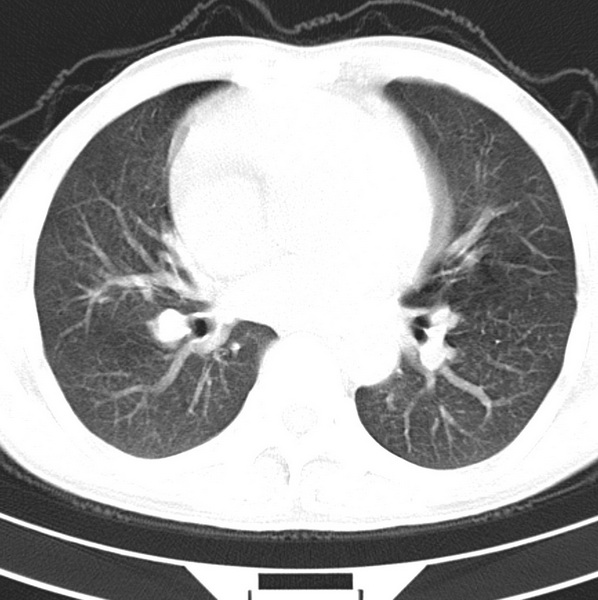

男、48、咳嗽。

胸片示双肺纹理紊乱,行胸部ct检查。

右肺下叶基底段结节影,双肺粟粒样阴影,ct值测量约-20hu左右,可能不准。

层厚层距为4mm左右,病灶轴面最大径约1cm左右。